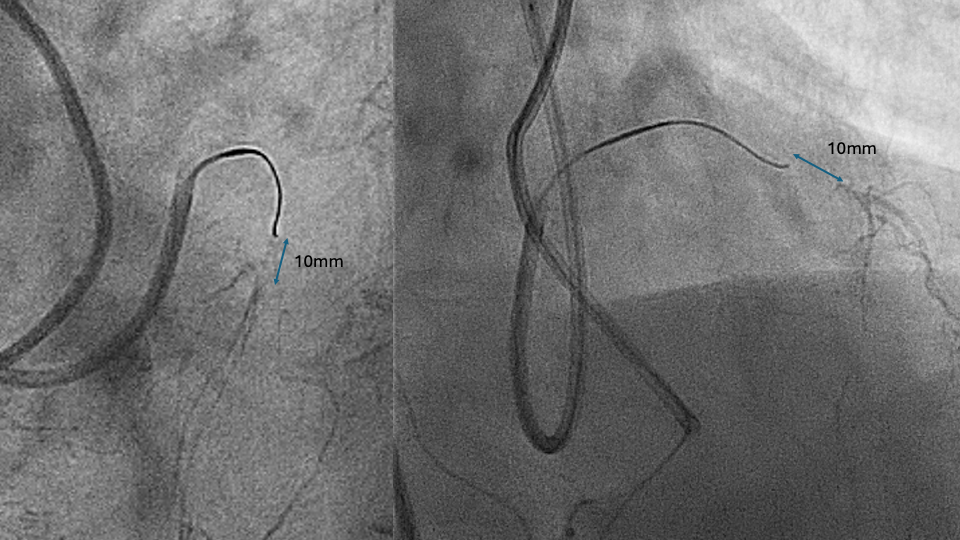

- Stop when the antegrade wire reaches 10 mm proximal to distal cap. Wires require longitudinal distance to change direction and wires perform better when wiring through virgin territory. Therefore, operators should stop 10 mm before they reach the distal cap to allow adequate longitudinal distance for the wire to be directed in virgin territory towards the distal cap (Figure 1).